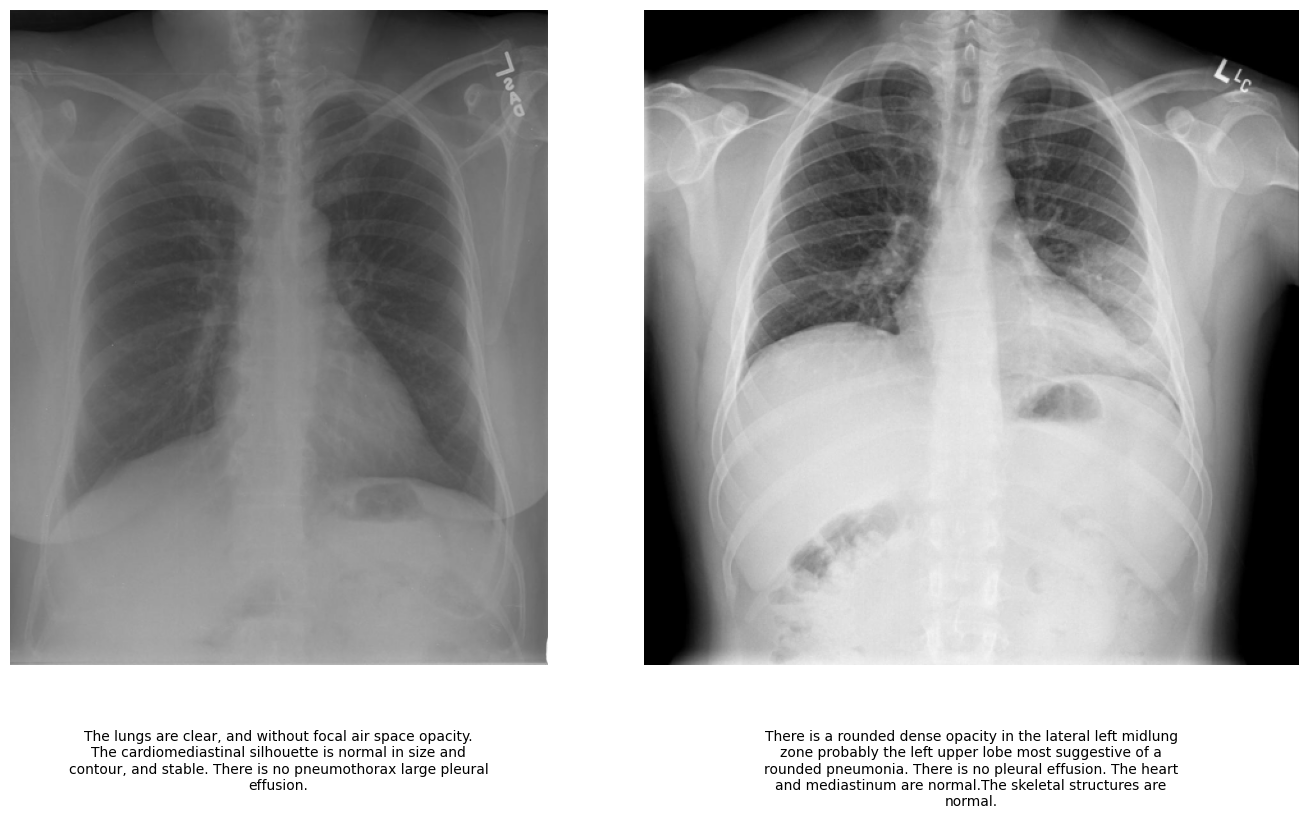

We have used the IU-Xray [47] dataset which is a publicly available collection of radiographic images paired with their corresponding radiology reports. This dataset is widely used for research in medical imaging. The dataset comprises a total of 5,910 chest X-ray images along with their associated findings in the form of radiology reports. Each image in the dataset is accompanied by a detailed textual description that provides diagnostic insights. Figure 2 presents two sample cases from the dataset: one depicting a normal chest X-ray and the other showing an abnormal case, along with their corresponding reports.

Refer to caption

Figure 2: Sample X-ray images and corresponding findings in form of report from the IU-Xray dataset. This report is being treated as the ground truth.